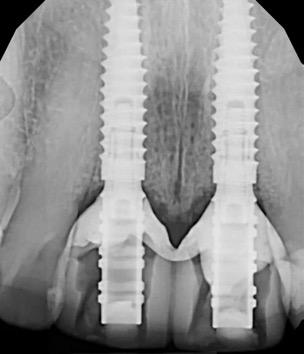

Fig 2. Intraoral radiograph indicating tooth structural loss extent.

Fig 4. Alveolar bone imaging. The alveolar bone was intact, and the alveolar crest was approximately 4mm apical to the restorative margin.

Fig 6. BioHorizons Tapered Pro Conical implants of 3.8 x 15mm placed according to the plan.

Fig 9. Periapical radiograph for verification of proper seating of the scanbodies.

Fig 13. Radiograph of implants, grafts and Provisionals.